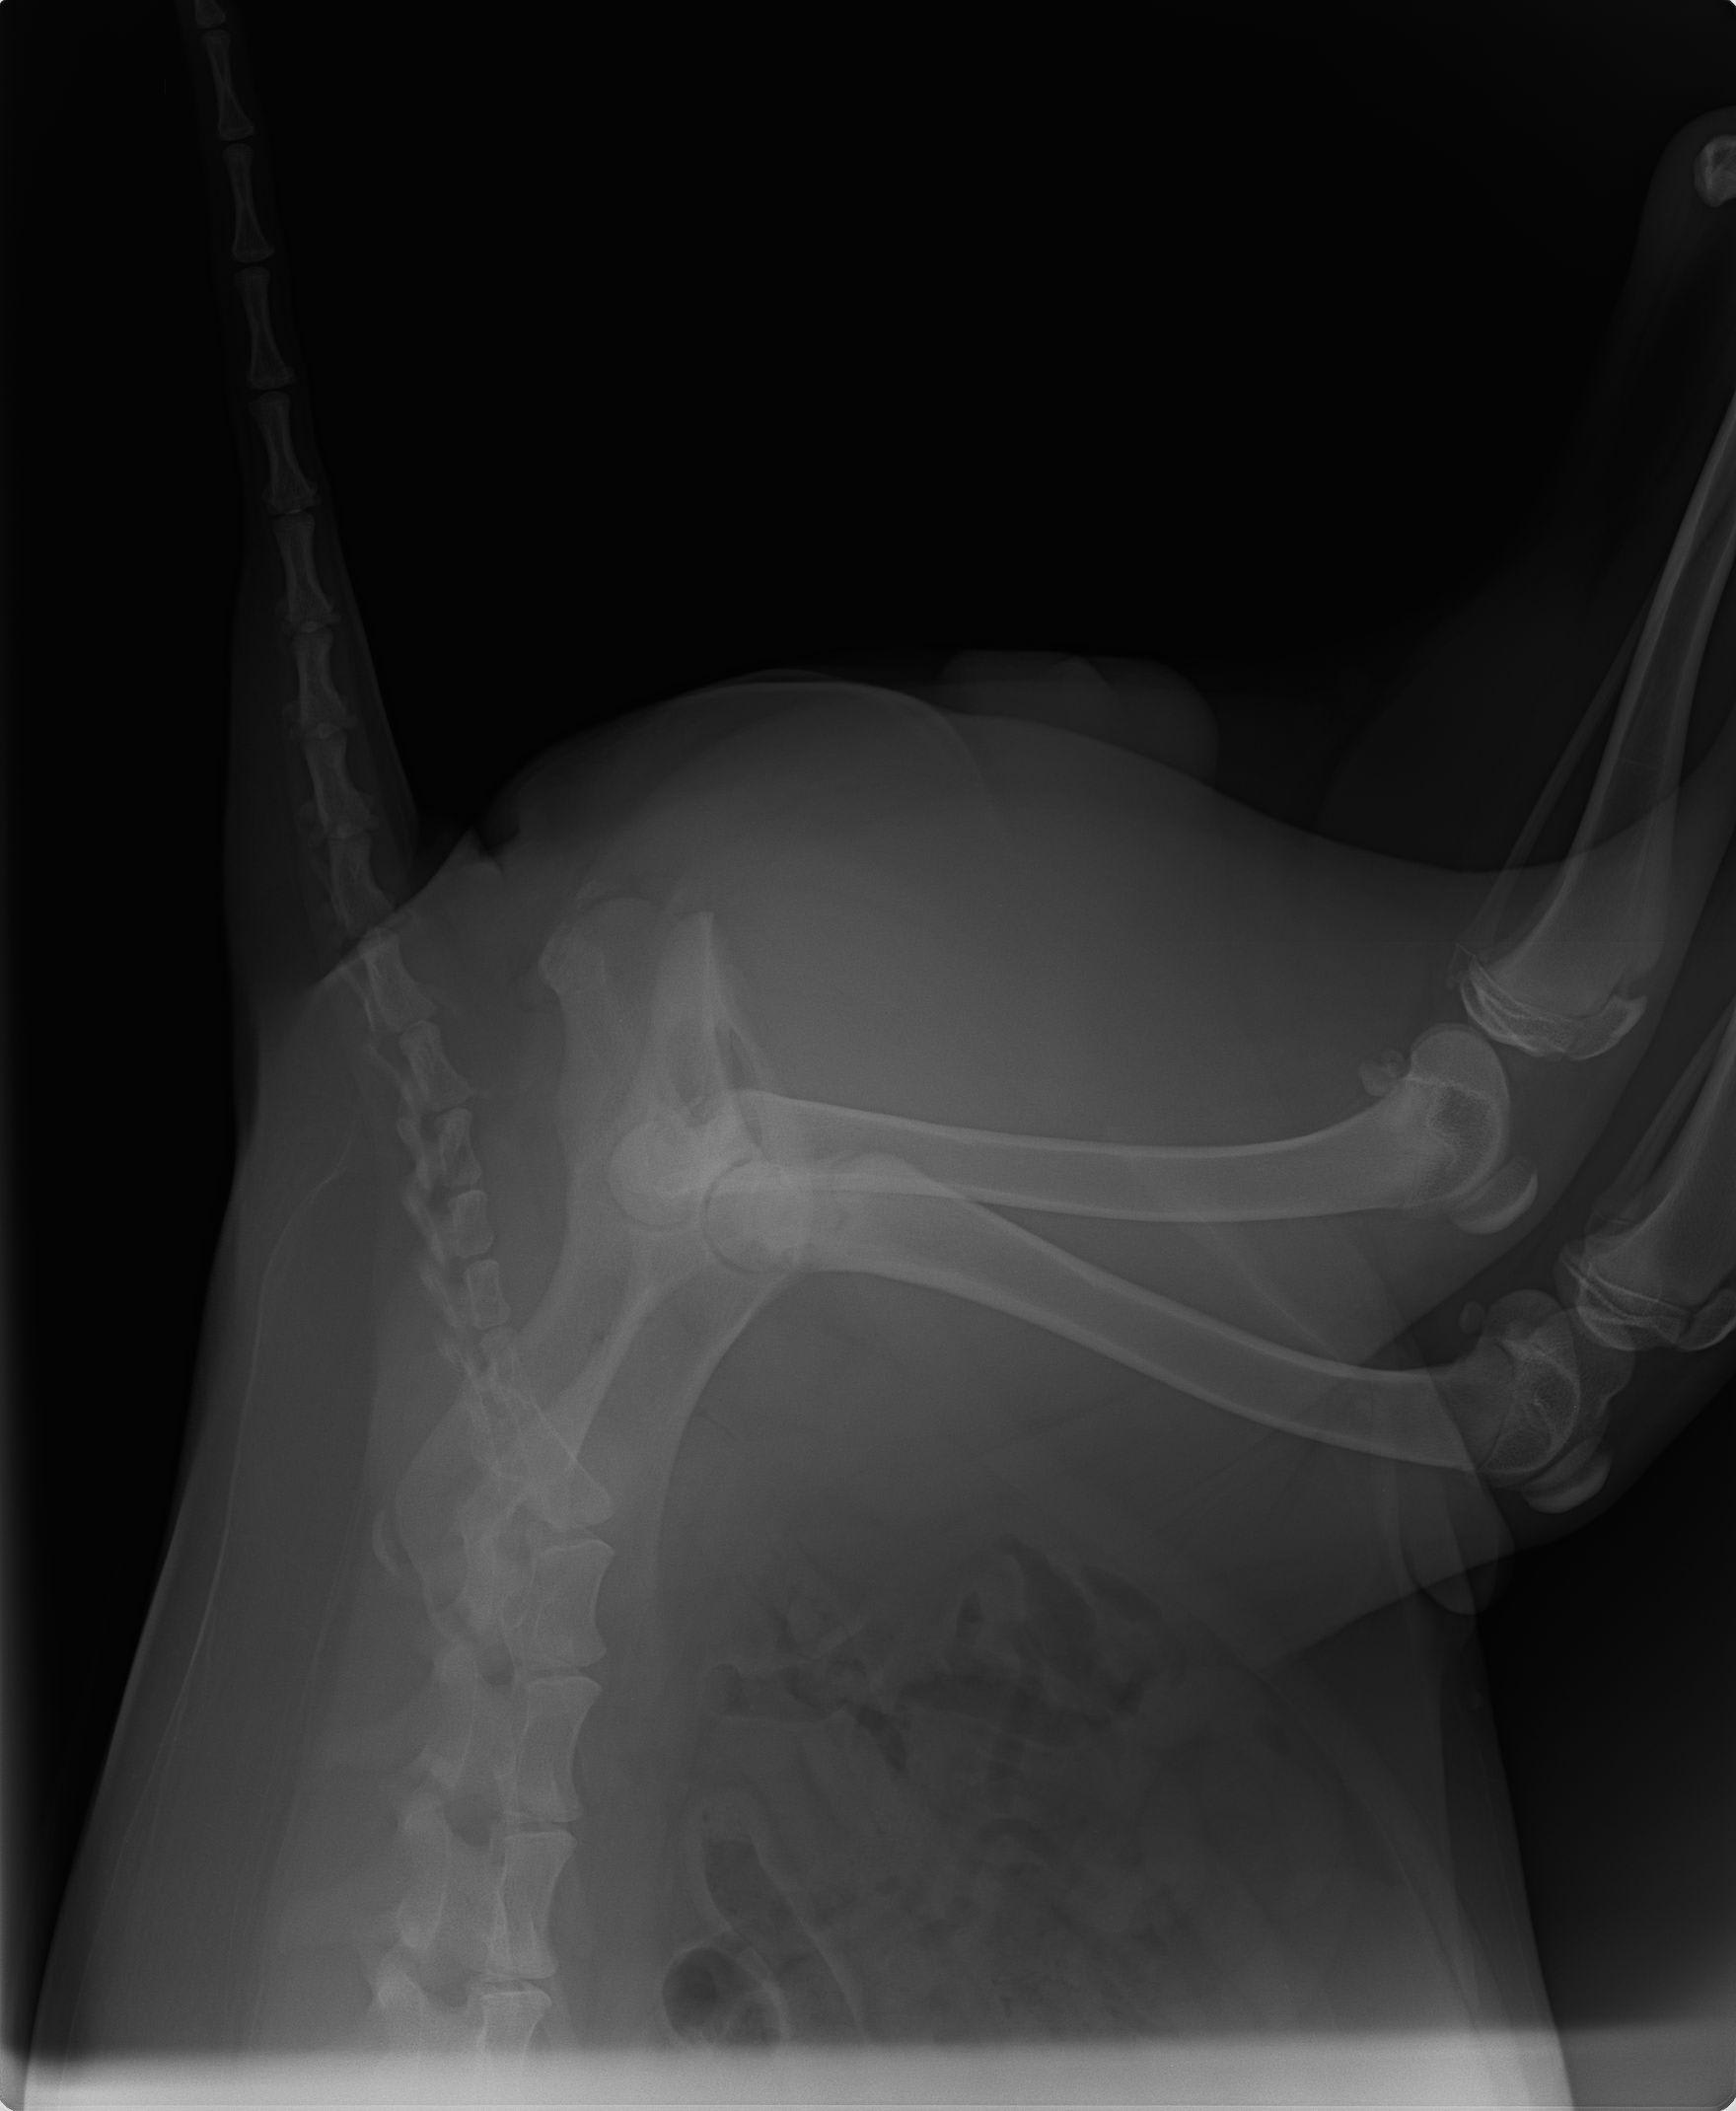

My dog has hip dysplasia in both of his back legs. He is labrador 33kg /75 lb weight. I consulted nearly all my vets in my state but all said he has to go through surgery which will cause lameness for his entire life and as its in both legs it quite risky too. They say that the surgery is about pain but he does not feel any pain he runs around the house all day. I don't want him to remain lame his entire life as he only 10 months old. All vets say surgery is only option. So i am confused...

Hello, sorry to hear about Shiro. He does indeed have hip dysplasia as is evident in his x-rays. This diseases does indeed require surgical correction, but only if Shiro seems to be in discomfort. Hip Dysplasia results in secondary osteoarthritis which in the long term can impact your pets ability to walk and overall comfort. There are two different procedures with regards to surgery, an FHNO were we remove the femoral head and neck or a total hip replacement were we replace the ball and joint with metal implants as they do in humans. Ultimately, the best contributor to decreasing osteoarthritis in dogs is by maintaining an overall low weight and lean body condition score. Obese pets with hip dysplasia tend to do worse. Now, with regards to surgery, it does not need to occur now, typically with either surgery, we want pets to be fully developed so that their bones are fully grown and they have developed all of the musculature. I would recommend asking your veterinarian to refer you to an orthopedic surgeon who may be able to better assist you with Shiro's hips dysplasia. Hope this helps and best of luck.